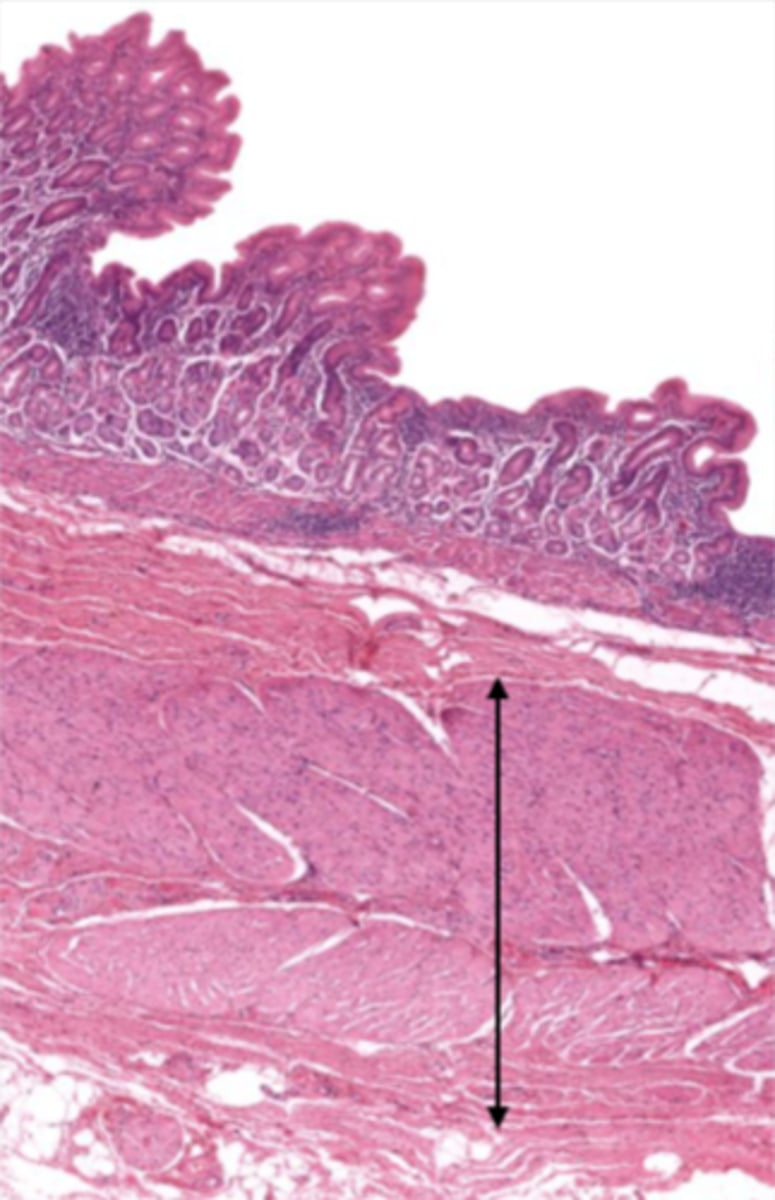

esophagus (histology)

lumen (esophagus)

mucosa (esophagus)

mucosal epithelium (esophagus)

stratified squamous epithelium

what kind of epithelium lines the mucosa of the esophagus?

lamina propria (esophagus)

muscularis mucosa (esophagus)

submucosa (esophagus)

contains glands and blood supply

muscularis externa (esophagus)

serosa/adventitia (esophagus)